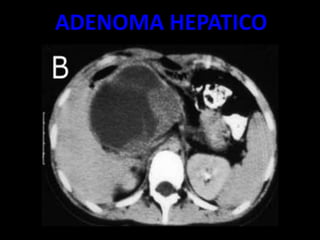

ADENOMA HEPATICO

• SUELEN SER LESIONES

REDONDEADAS

• SÓLIDAS GENERALMENTE ÚNICAS

• BIEN DELIMITADAS.

• OSCILA ENTRE 6 A 15 CM